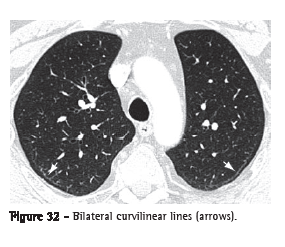

Subpleural curvilinear line (linha curvilínea subpleural)

The subpleural curvilinear line is a curvilinear opacity of 1-3 mm in thickness, located in the subpleural region and having a parallel distribution over the pleural surface (Figure 32). It is a nonspecific sign for atelectasis, edema, fibrosis or inflammation.(3,7)